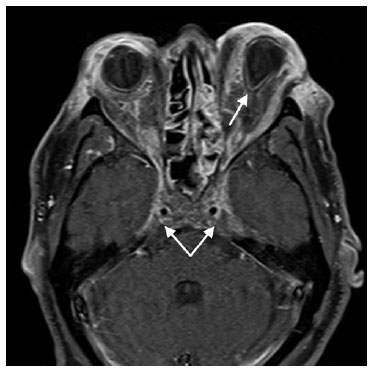

After 2 weeks, the patient’s VA was 20/40 in the right eye and NLP in the left eye, with improvement of clot burden on imaging (Figure 3). Heparin was transitioned to warfarin, and the IV antibiotics were continued for 6 weeks. At 6 weeks, the patient was discharged on warfarin.

02-fig03.jpg)